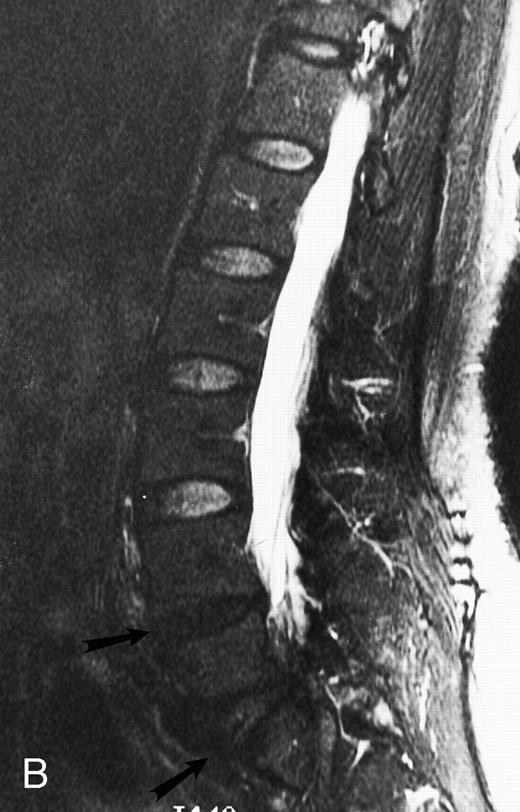

An 8-year-old boy with Burkitt's lymphoma and diffuse marrow involvement. Fat-suppressed, T2-weighted fast spin echo (3000/96, TR/TE) sagittal MR image of the lumbar spine shows heterogeneous signal intensity of the bone marrow and epidural extension of tumor (arrowheads) at the level of L5 and L2, with apparent preservation of the vertebral cortex.